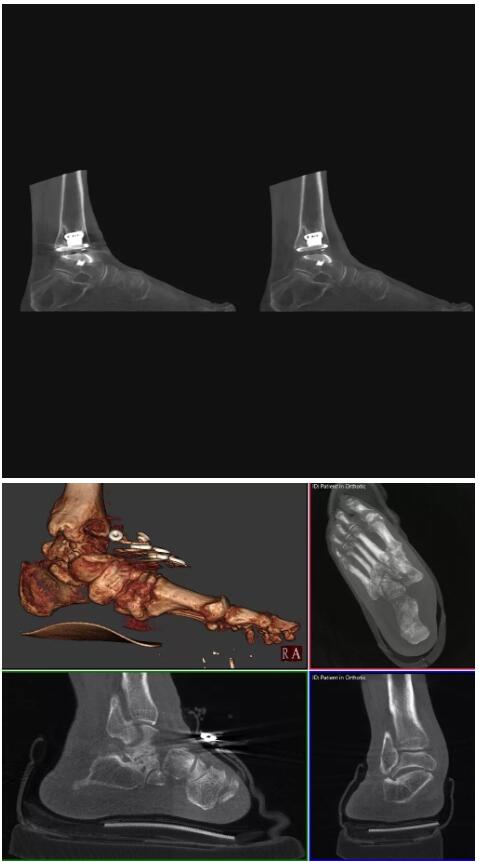

另外一款被稱為世界上最小的CT,它的重量僅300磅,不僅能夠掃查足部,還可以檢查膝蓋和上肢等。

與上面介紹的CT一樣,它同樣具有輻射低、占地空間?。?3*36)的特點,隨開隨用(支持直接接入墻上的插座)。

這款CT使用非常方便,通過上下移動保持與患者的手臂或者雙腿齊平,掃描快速,僅需要30秒左右就可以完成掃查。

以上介紹的CT均來自國外同一家公司,這些CT均配置了可視化軟件,可以進行切片、3D重建以及大型CT附帶的所有典型的操作功能。

以下是這些“特立獨行”的CT所拍出來的圖像: